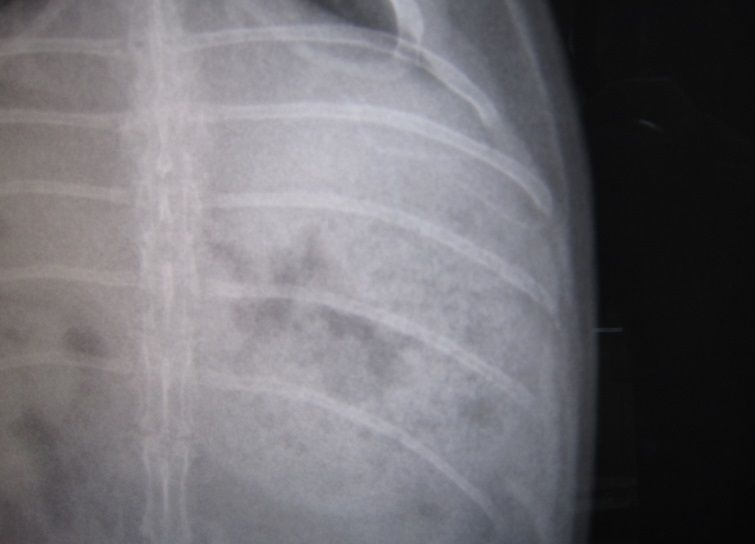

昨夜からの流れを話しし、診察、レントゲン

閉塞所見はありません

もちろん心臓も小さくなってないし

若干のガスはあれど、強いて指摘するならばレベル

で、ちゃんと出番待ちしとる(。・m・)

いつも感心するウンコ影“〆( ̄▽ ̄*)

と、胃腸に大きな問題はなさげだったのだが…

脂肪、すご過ぎやん…( ̄ェ ̄;)